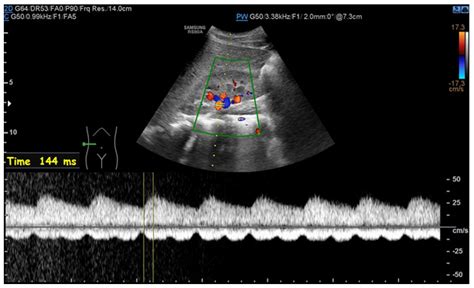

• tardus parvus waveform ultrasound image

• pulsus parvus et tardus waveform

• tardus parvus waveform ultrasound carotid

• tardus parvus ultrasound

• what is tardus parvus waveform